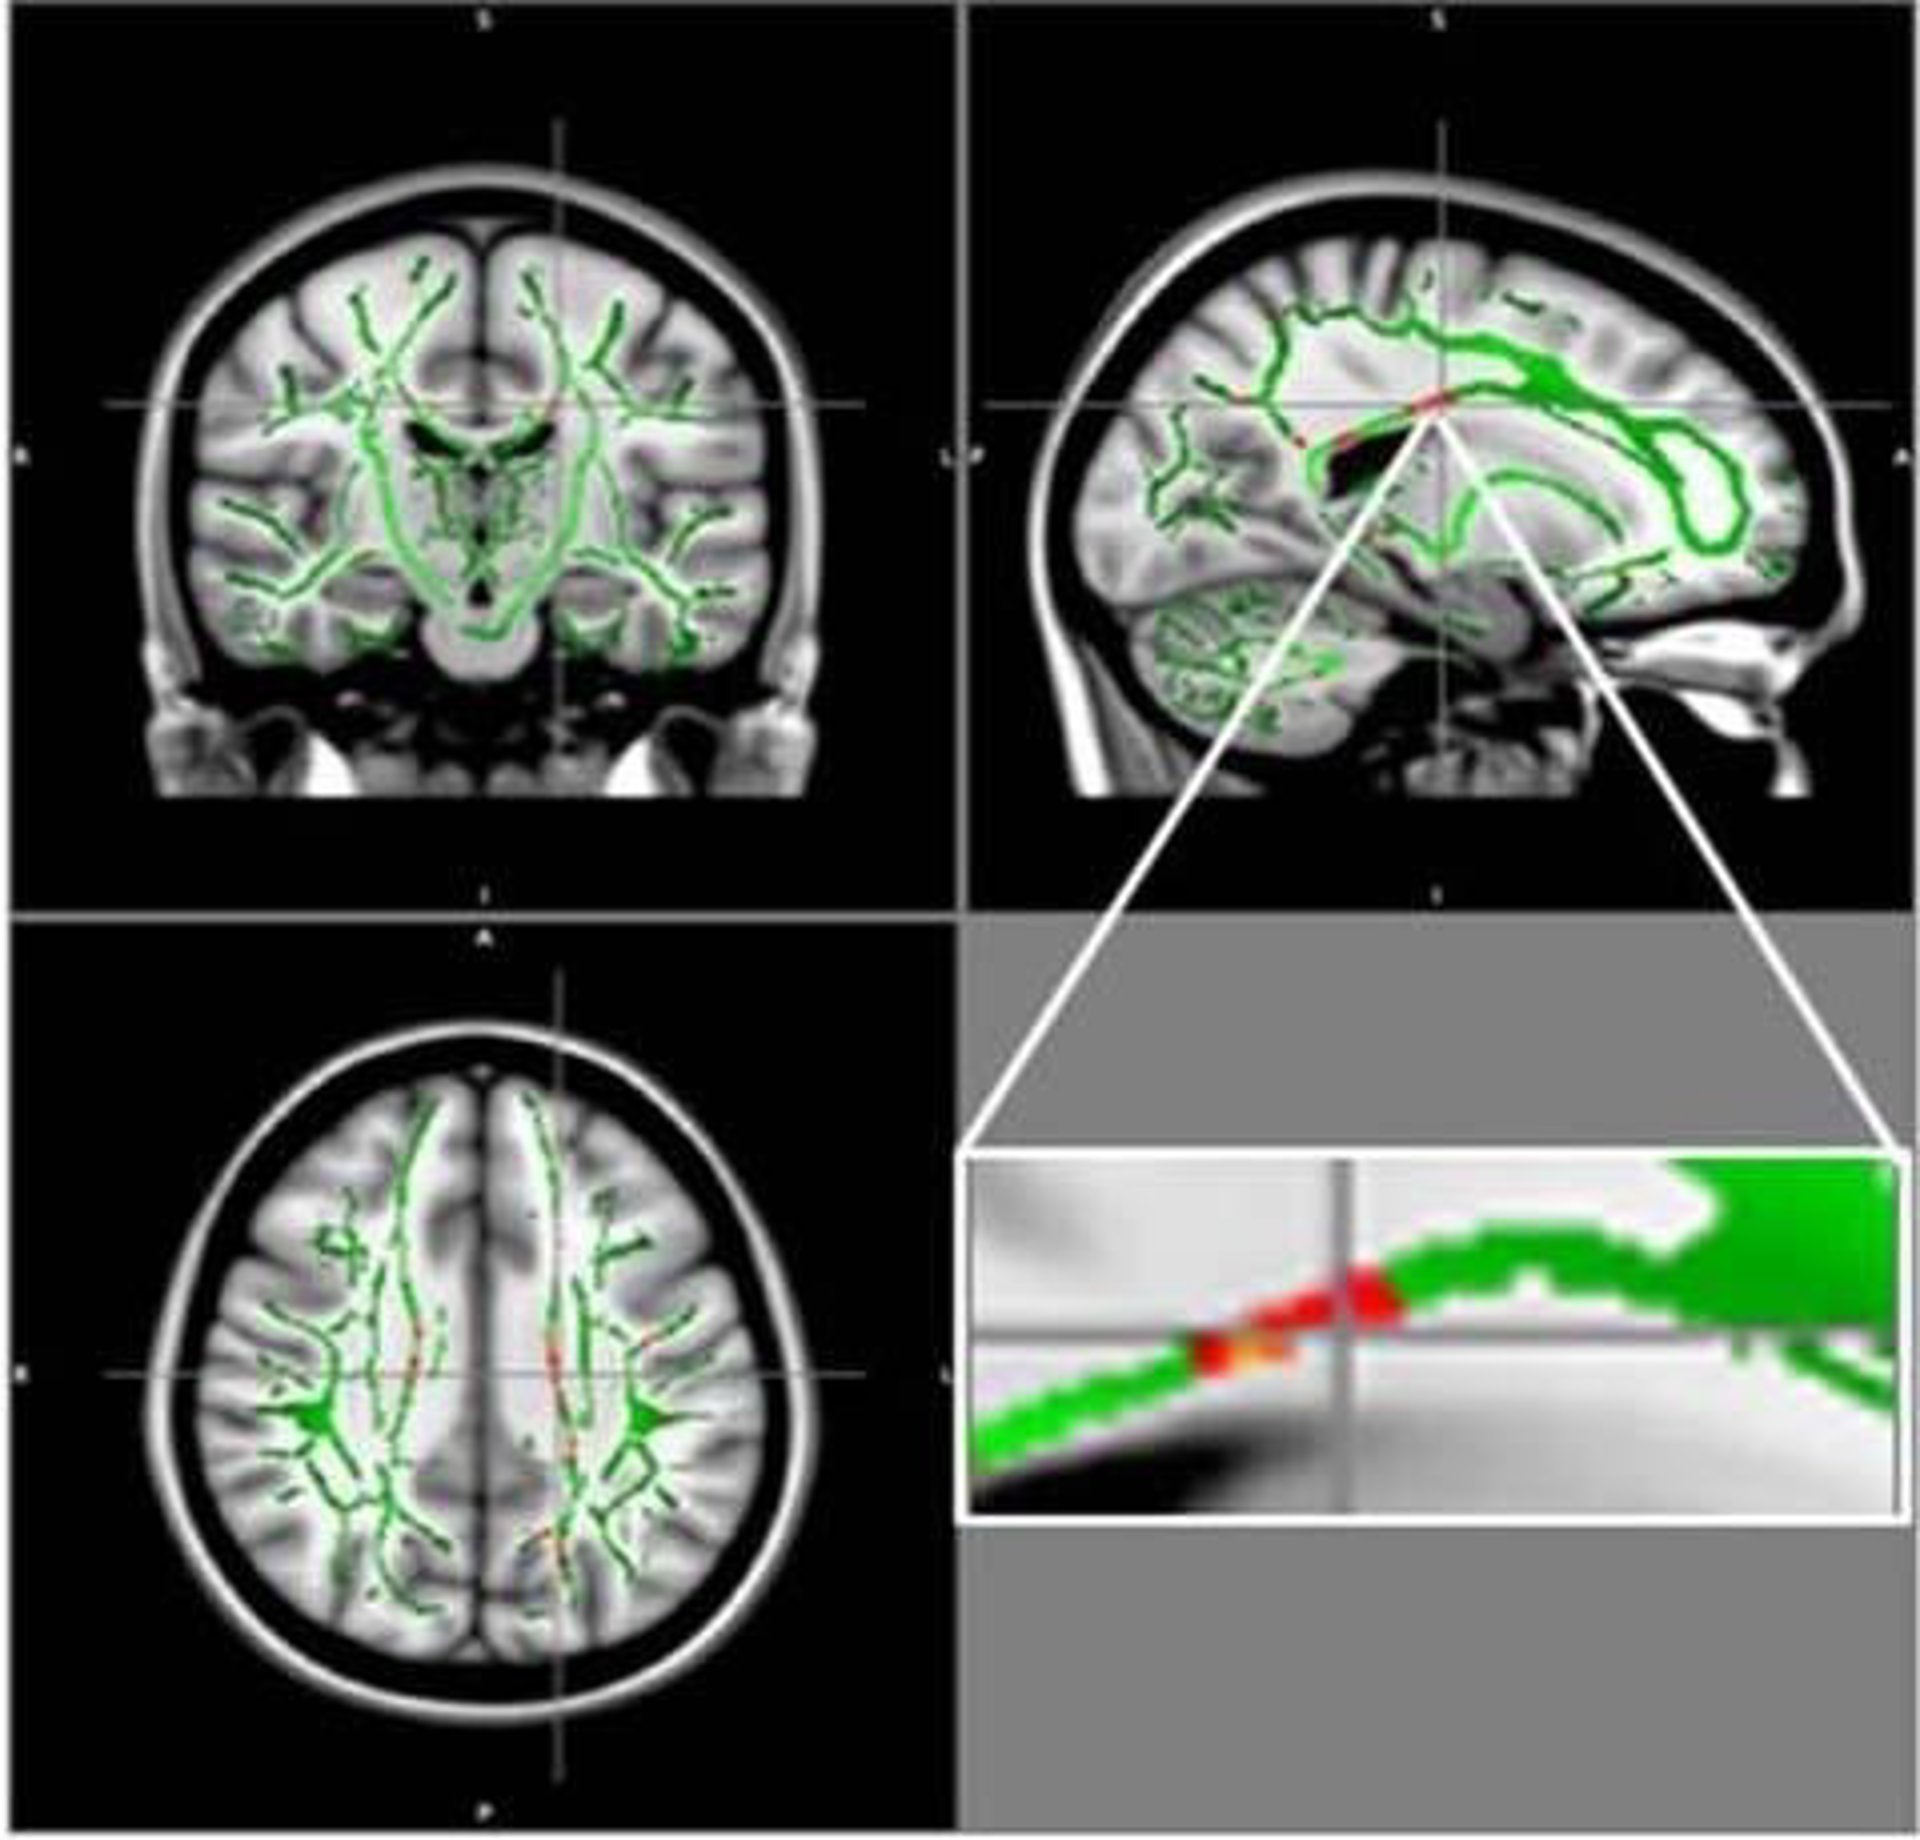

En su nuevo trabajo, que se presentará la próxima semana en la reunión anual de la Sociedad de Radiología de Norteamérica (RSNA, por sus siglas en inglés), los investigadores utilizaron la resonancia magnética por tensores de difusión (DTI), una técnica que rastrea la difusión del agua a lo largo de los tractos de materia blanca que transportan la señal del cerebro.

Los investigadores compararon los resultados de la DTI de 59 adolescentes obesos y 61 adolescentes sanos de 12 a 16 años de edad. A partir del DTI, los investigadores derivaron una medida llamada anisotropía fraccional (AF), que se correlaciona con la condición de la materia blanca del cerebro. Una reducción del AF es indicativa de un aumento de los daños en la materia blanca.

Los resultados mostraron una reducción de los valores de AF en los adolescentes obesos en regiones localizadas en el cuerpo calloso, un conjunto de fibras nerviosas que conecta los hemisferios izquierdo y derecho del cerebro. También se encontró disminución de la AF en la corteza orbitofrontal, una región cerebral relacionada con el control emocional y el circuito de recompensa. En ninguna de las regiones cerebrales de los pacientes obesos había aumentado la AF.